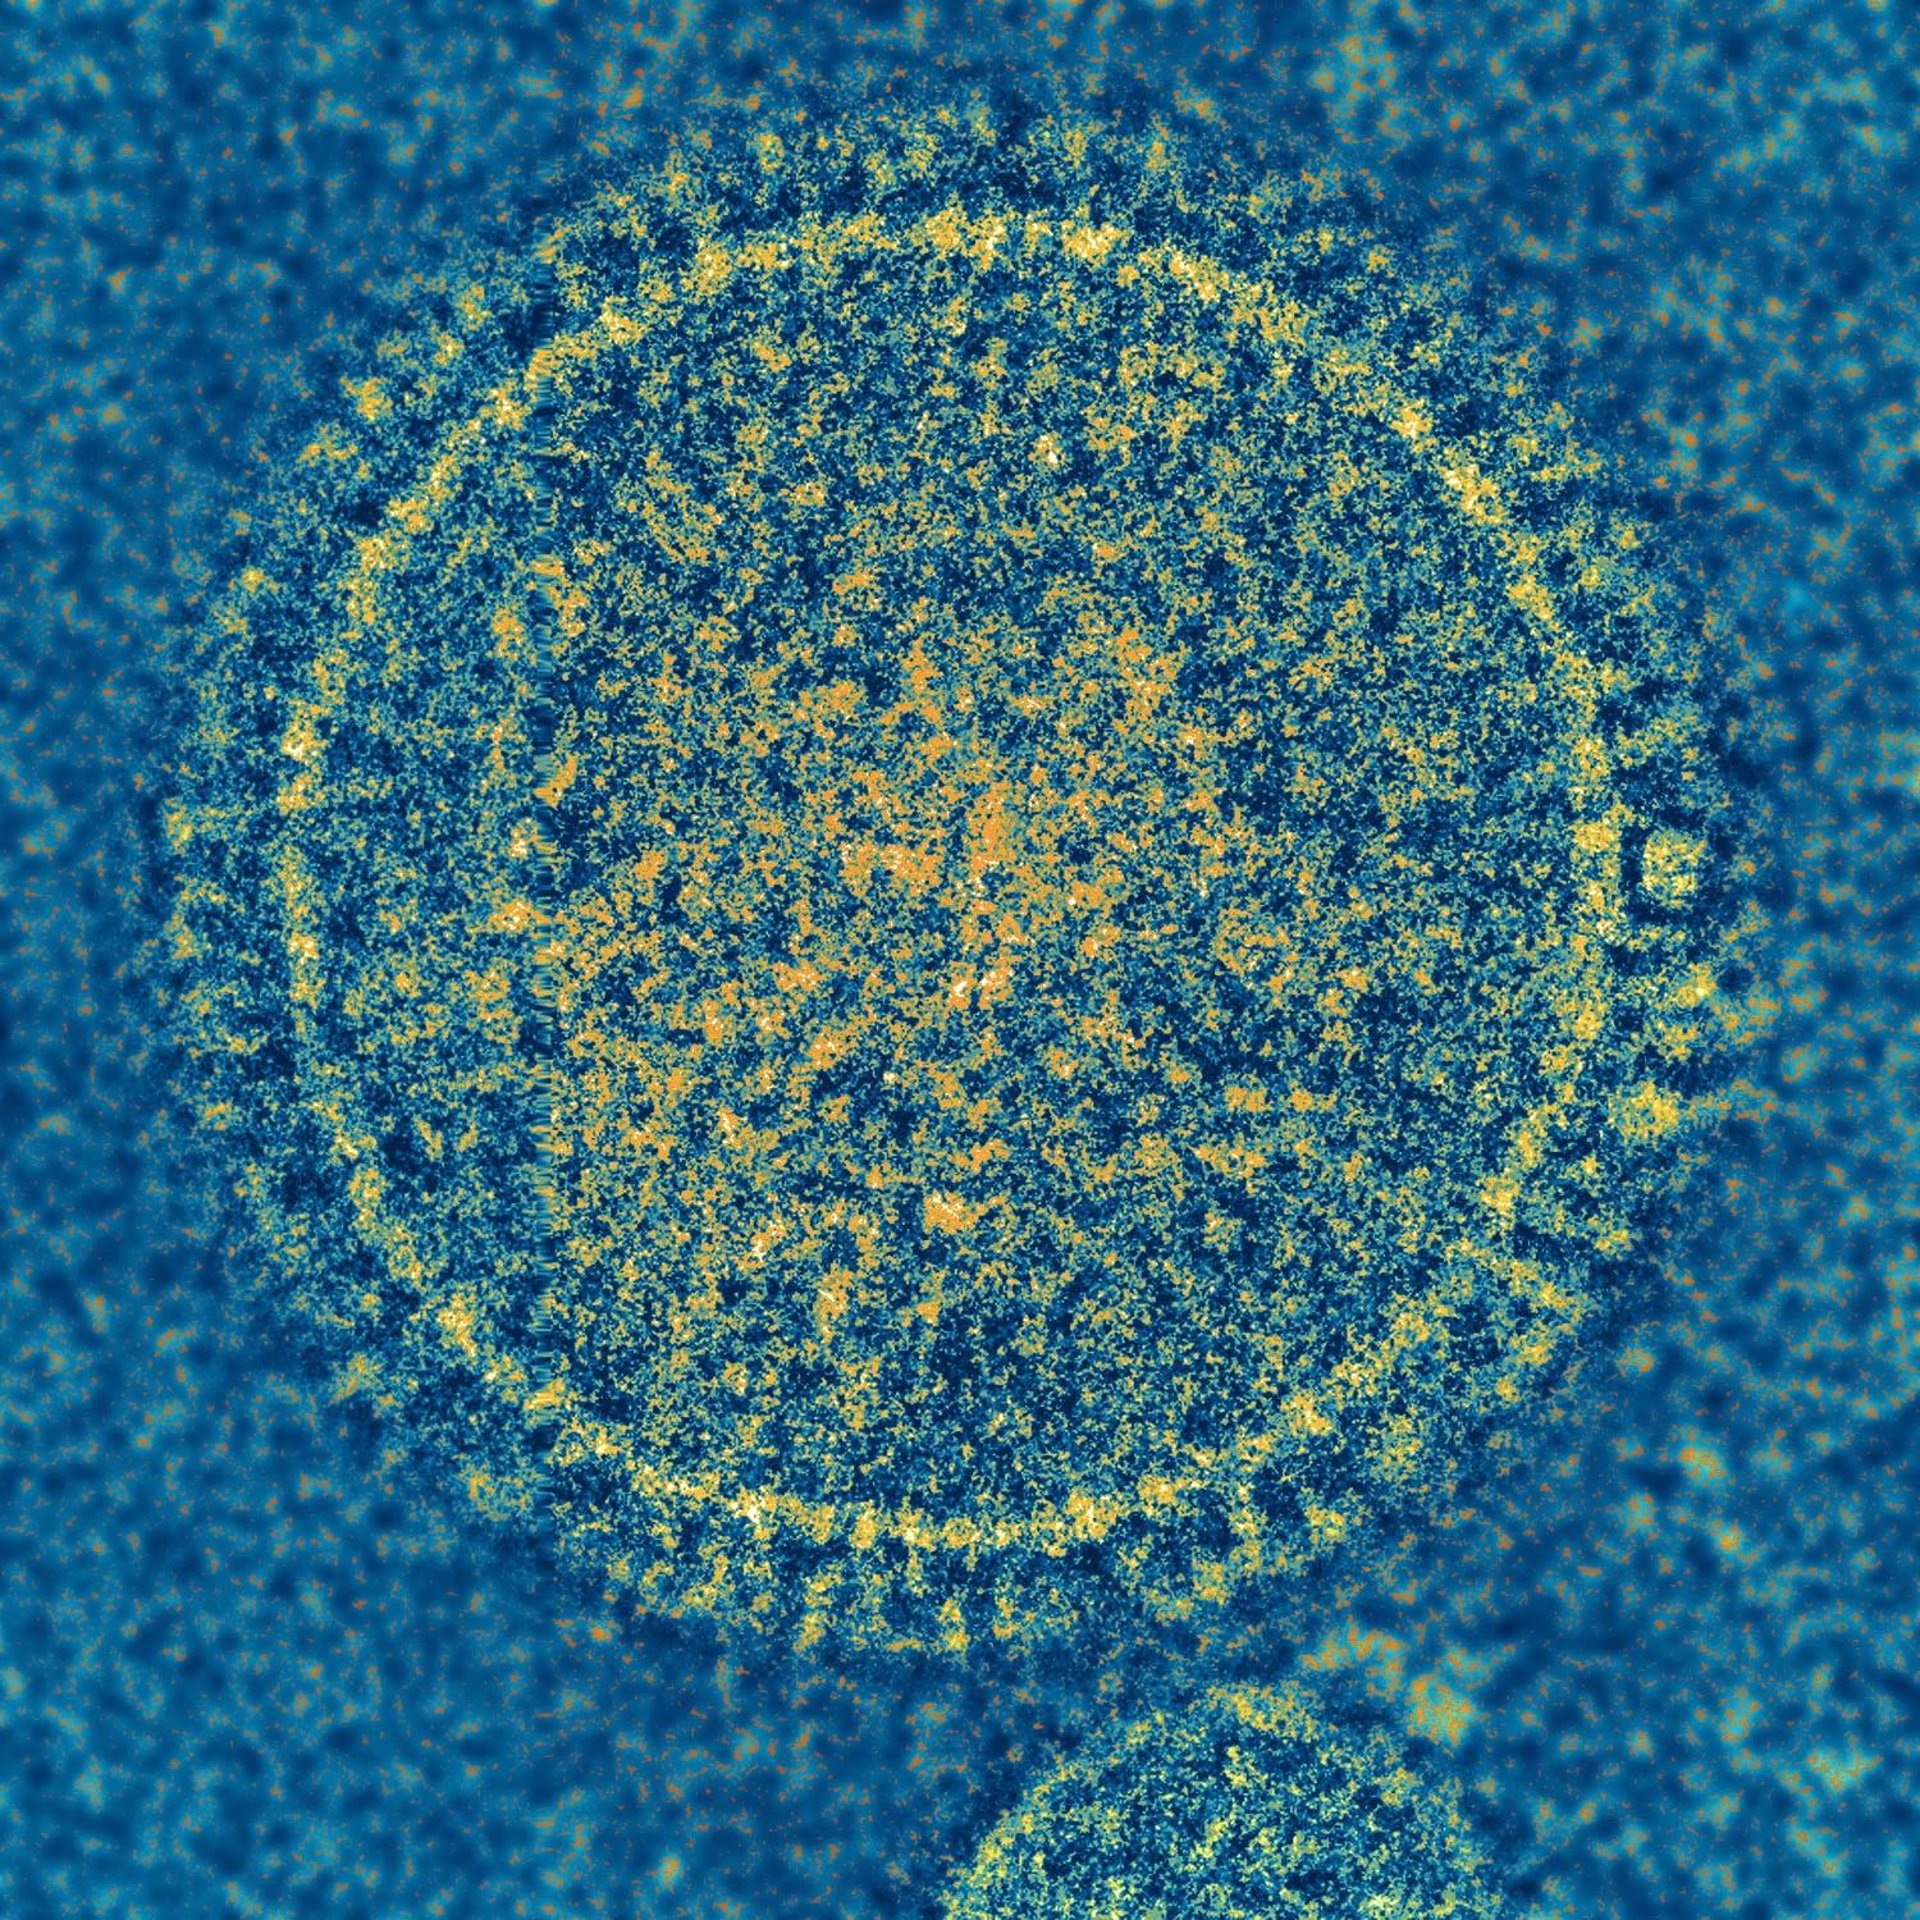

Virus sincitial respiratorio

NIAID

Científicos del Instituto de Alergia y Enfermedades Incecciosas de los Institutos Nacionales de Salud (NIH, en sus siglas en inglés) de Estados Unidos han desarrollado una vacuna experimental contra el virus sincitial respiratorio (VSR), la principal causa de enfermedad y hospitalización en los niños muy pequeños, provoca altos niveles de anticuerpos específicos de RSV cuando se probó en animales, según un informe publicado en la revista 'Science'.